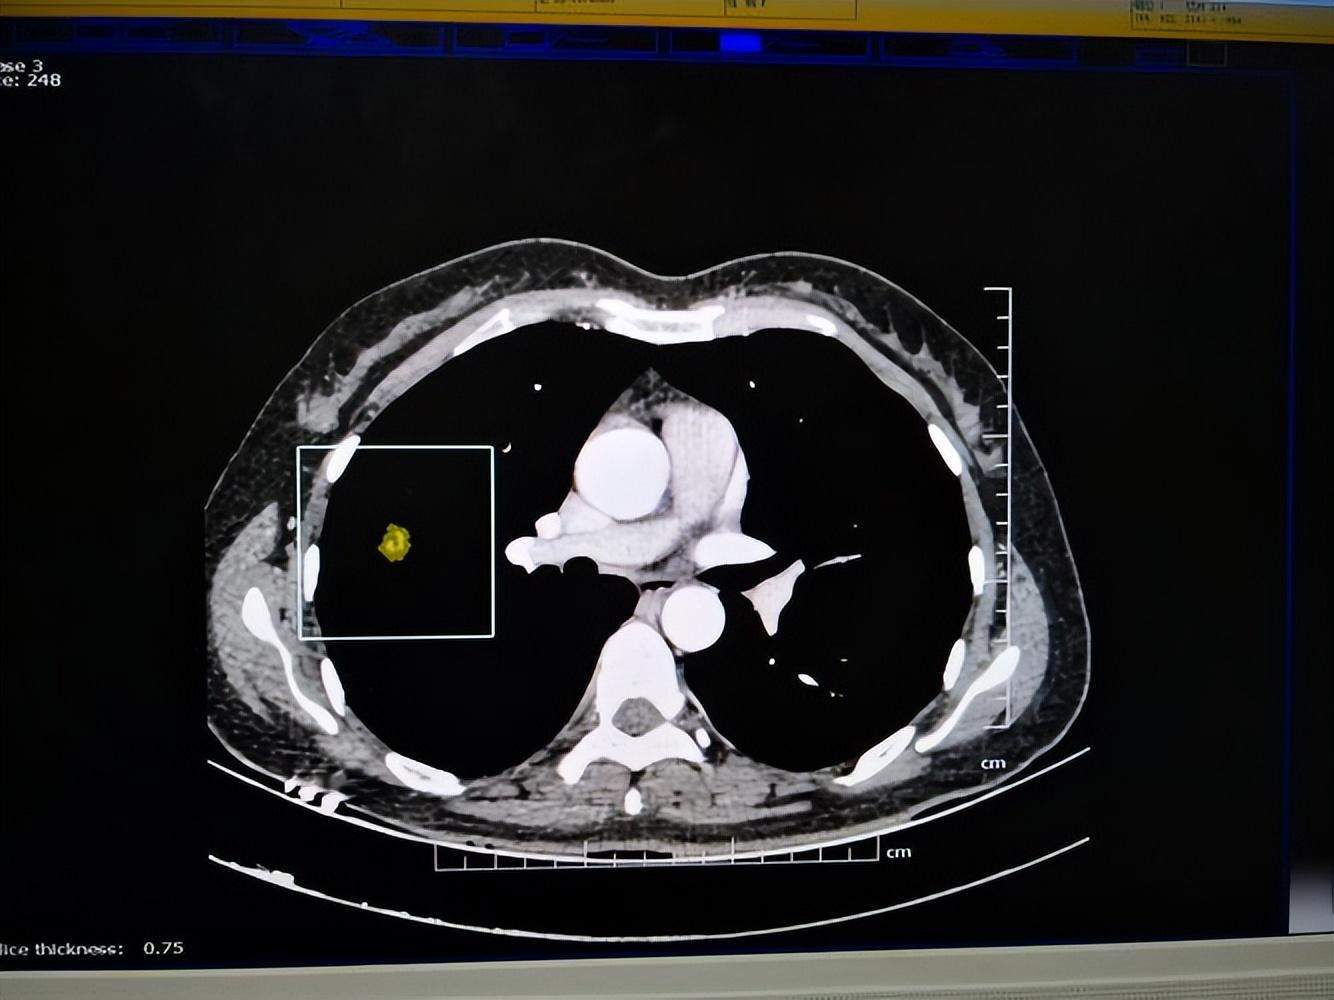

薄层CT影像

薄层CT是重建方式,不是扫描方式。平时扫描用5mm层厚扫描,很微小病灶、<5mm病灶、小结节、一个肿瘤或者小腔隙性梗死,5mm层厚时看不见。利用重建技术切薄,如西瓜一样切成薄片,5mm切成2.5mm、1.25mm、甚至0.625mm。微小结节或者微小结节病变中细节问题,如边缘、密度、与周围关系、有没有脂肪密度、有没有钙化影子等,可以看得非常清楚。价格一般在500元左右。